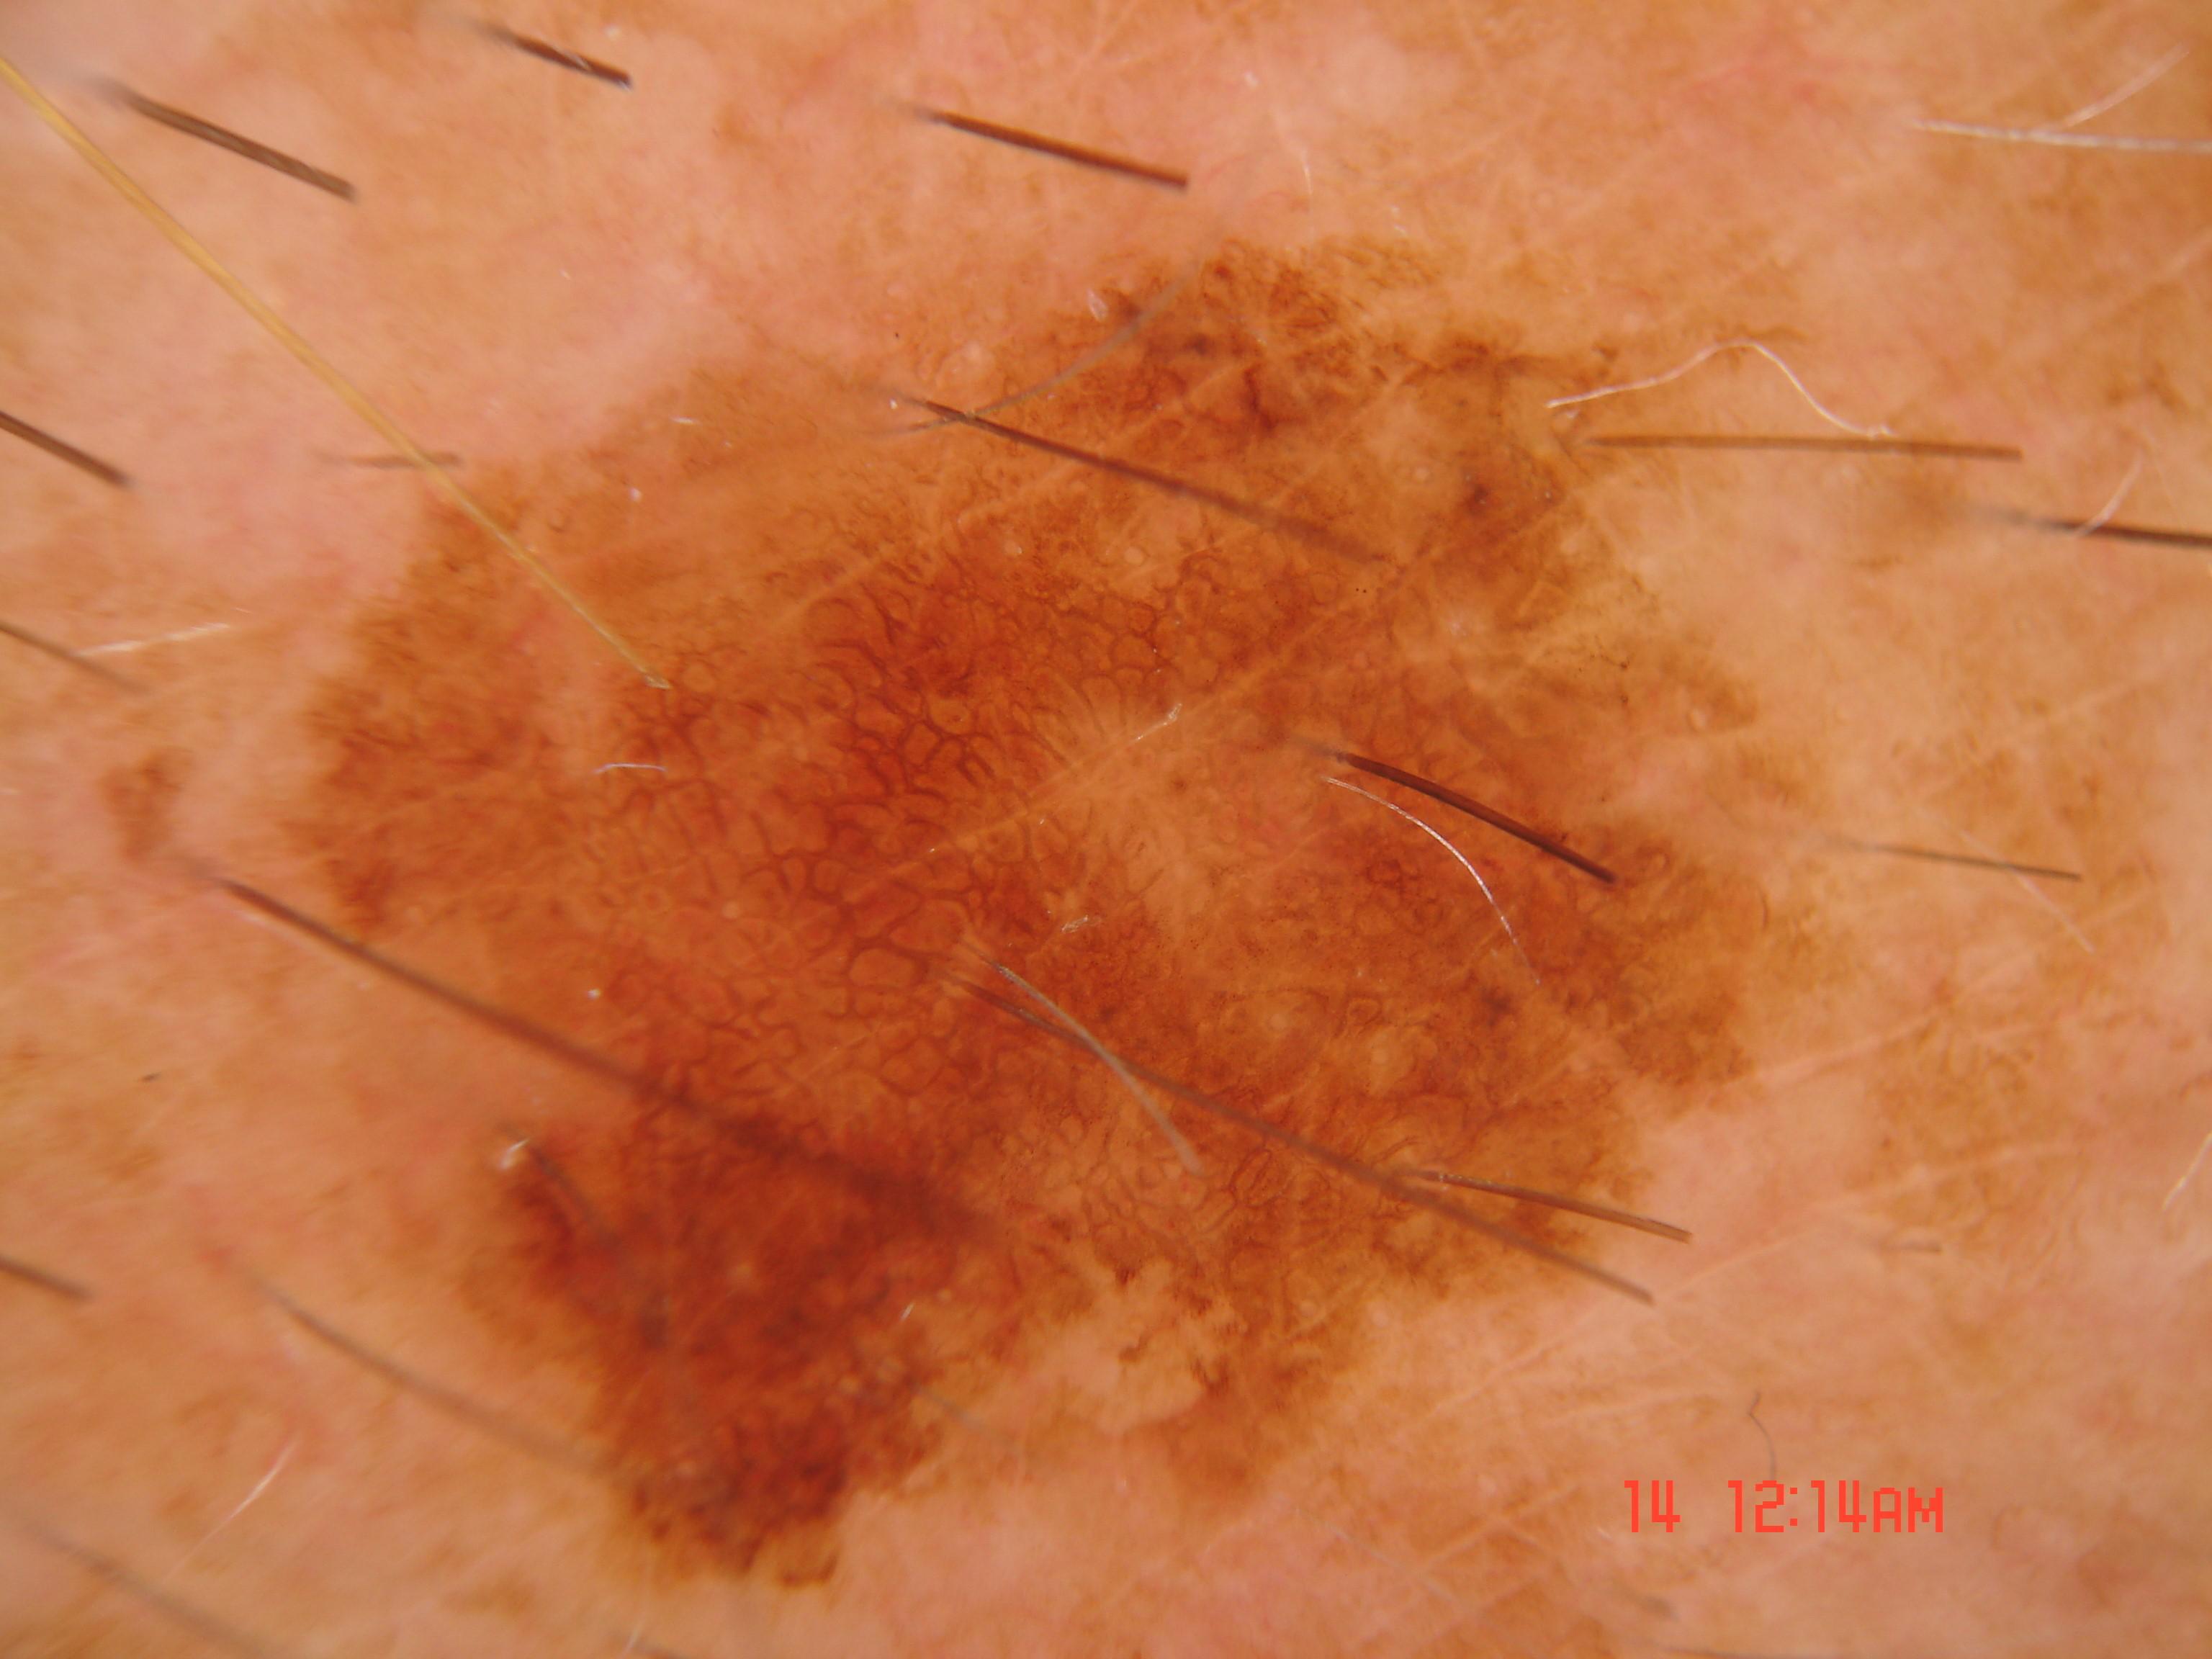

Biopsy-confirmed melanocytic and non-melanocytic skin lesions. This dataset includes over 500 melanomas. Many images have polarized and contact variants.